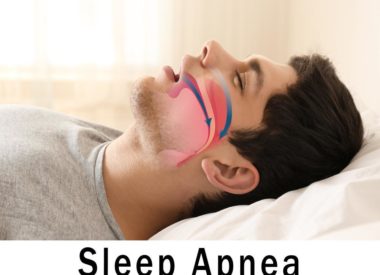

Will Sleep Apnea Cause Insomnia?

Everyone has trouble sleeping at some point in their life. A late-afternoon latte, an overly indulgent dinner or nerves about an upcoming work milestone can keep you up into the wee hours of the night. The next day may not be one of your best –- you might be irritable, exhausted and unfocused — but…

Sleep Apnea Raises Your Risk of Sudden Cardiac Death: Get the Facts

You may have heard of sleep apnea, but do you really know what it is? Far from a harmless sleep disorder that keeps you from a sound night’s rest, sleep apnea can lead to serious health complications, including sudden cardiac death. According to the American Sleep Apnea Association, 22 million Americans suffer from sleep apnea.…